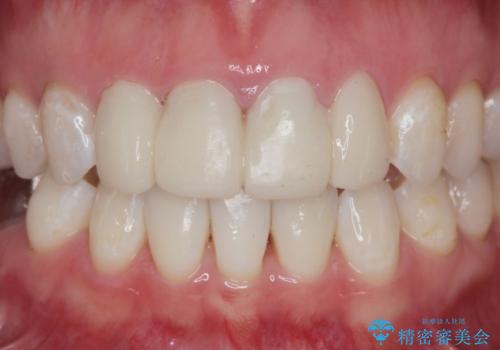

仮歯のまま放置していた前歯をセラミックに

- 仮歯のまま放置してしまい、変色を改善しきれいなセラミッククラウンをいれたい、と希望され来院されました。

特に虫歯の再発や神経の症状等問題を認めなかったので、審美的に優れるセラミッククラウンに仮歯を置き換えていきます。

- 52.8万円(ジルコニアクラウン×4・仮歯×4)費用は治療当時の料金となります